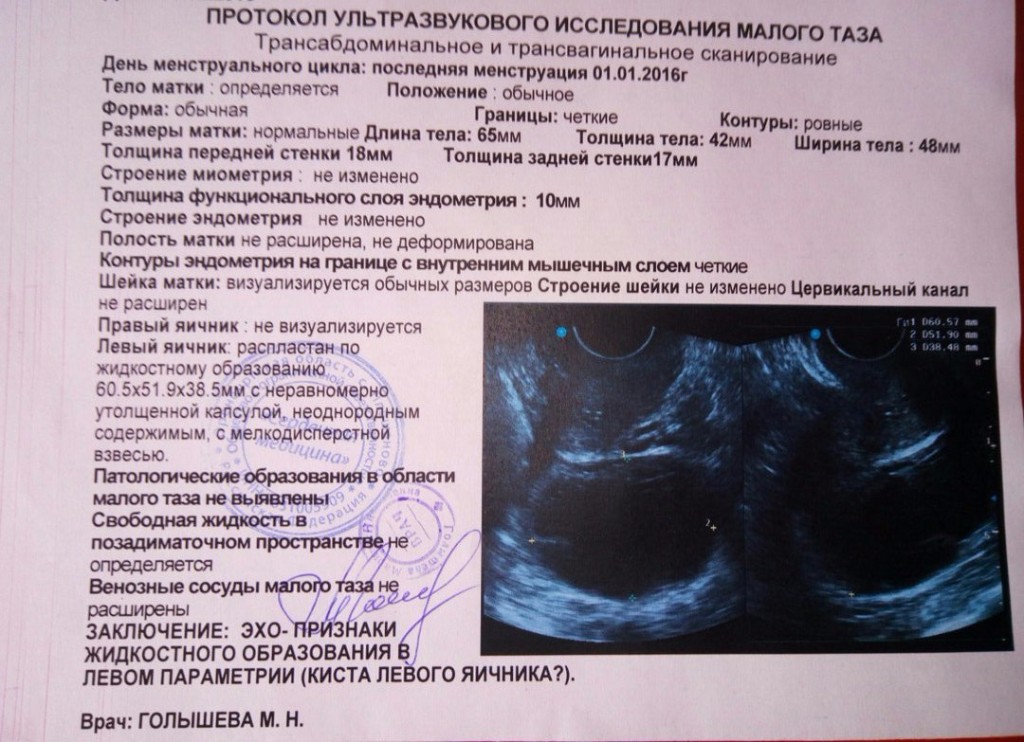

Медицинская визуализация: Признак Кюстнера-Чукалова

Раздел: Необычные решения